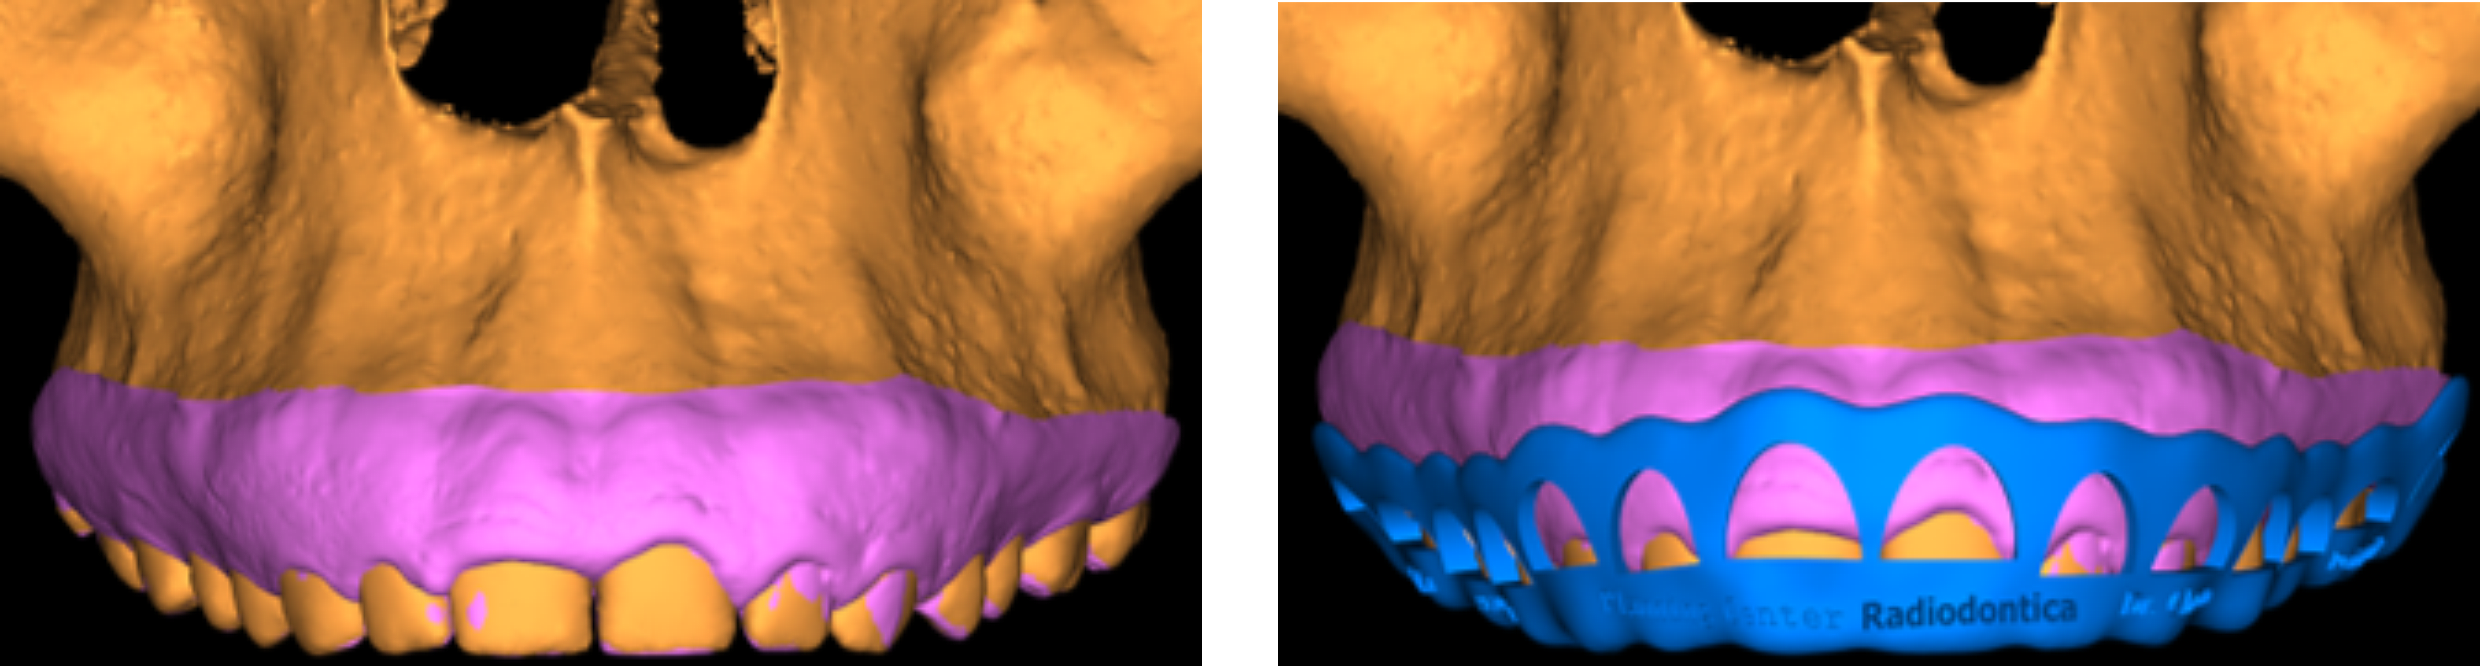

A Periodontia pode ser otimizada com a utilização dos recursos digitais, através do planejamento e o uso de guias para remoções ao redor dos dentes, aumenta a previsibilidade e a segurança da cirurgia. Esta guia é chamada de Perioguide, ou um guia para Periodontia.

Atualmente, diversas técnicas de cirurgia plástica gengival vem sendo utilizadas para aumentar a precisão dos recortes gengivais estéticos, mas engana-se quem pensa que a gengivoplastia é somente a remoção da gengiva em excesso. Cuidados pós-operatórios, tempo de repouso, cicatrização, simulações e muitos outros detalhes estão envolvidos neste procedimento cirúrgico que surpreende pela delicadeza e complexidade.

Com as transformações do sorriso com lentes de contato dental, a gengivoplastia ocupa os primeiros lugares entre os procedimentos estéticos mais realizados nos consultórios odontológicos. Além de alinhar gengivas, esta delicada cirurgia também pode ter funções tão distintas como eliminar o sorriso gengival ou melhorar os resultados estéticos de tratamentos com próteses dentárias, ou facetas de porcelana – ou simplesmente melhorar a harmonia do sorriso.